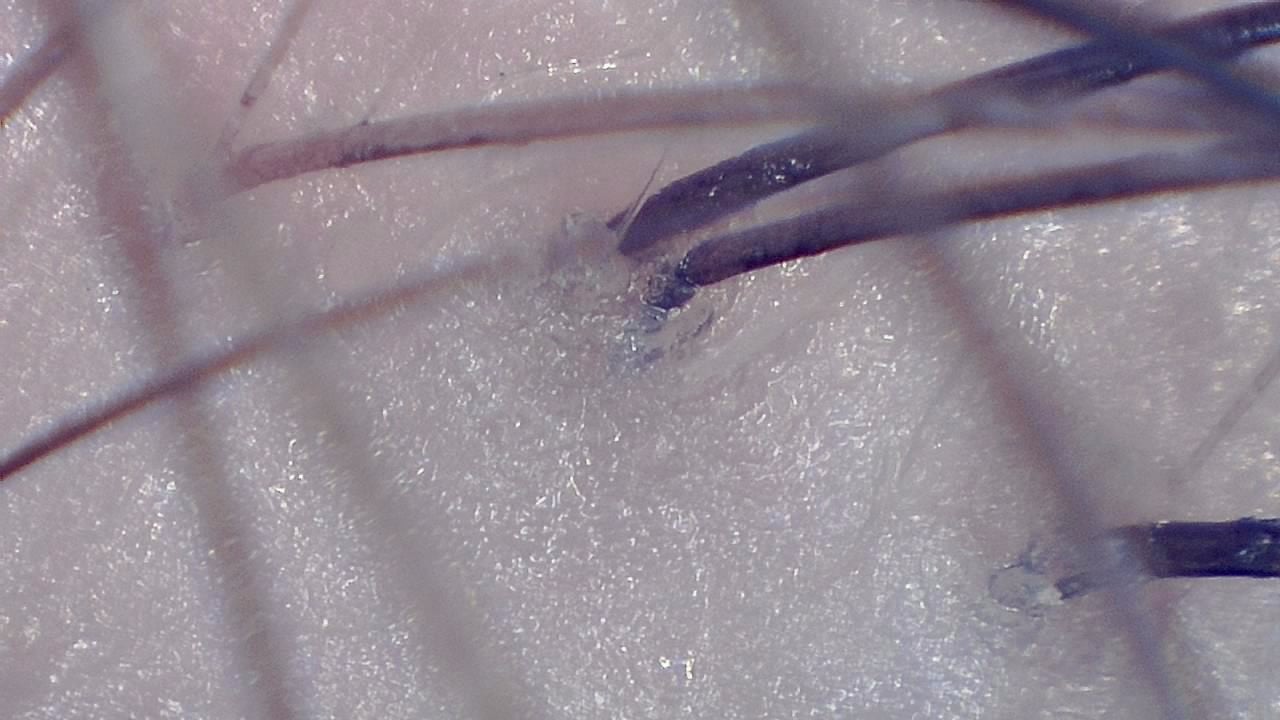

It is possible to visualize yellow dots, vellus hairs, follicular miniaturization, and other key dermoscopic markers used in the differential diagnosis of androgenetic alopecia, alopecia areata, and scarring alopecias.

Post hair-transplant follow-up

After a hair transplant, the trichologist uses the microscope to assess transplanted follicle growth, documenting monthly progress and adjusting post-care recommendations.